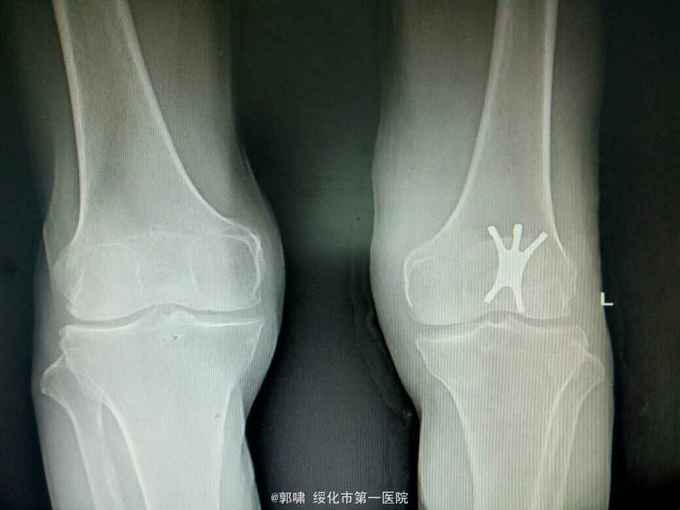

左膝关节摔伤,肿胀,畸形,活动受限一小时。收入院。患者于一小时前滑倒摔伤。当即倒地,左膝关节肿胀,畸形不能行走。门诊拍片示:左膝关节髌骨骨折,断端移位。门诊以左髌骨骨折收入院。

左膝关节肿胀,局部畸形,不能下地行走。浮髌试验阳性。拍片示:左髌骨骨折。

诊断:左髌骨骨折。立即予以腰麻下行切开复位内固定术。术中复位骨折,缝合筋膜,冰水浸泡髌骨爪约10分钟。待髌骨爪变软。选取合适大小的髌骨爪。应用记忆合金髌骨爪内固定。立即用40°温盐水热敷局部。使记忆合金加速抓紧。环抱。缝合爪齿二道,防止脱落。缝合关节囊,韧带组织。术毕。

应用记忆合金髌骨爪内固定髌骨骨折。手术时间基本在20----30分钟内都可以完成。局部损伤小。固定牢靠,确实。患者二个月就可以下地负重活动。具体手术技巧。一是髌骨爪提前用冰盐水侵泡10分钟左右。待记忆合金变软即可使用。二。固定牢靠后立即用40°温盐水热敷。使其快速抓紧。三,缝合爪齿,防脱。四如有粉碎,小的骨块可以缝合筋膜固定。有大骨块,最好环扎钢丝,或穿针固定,有时穿骨隧道钢丝捆扎。效果也不错。只要做到以上几点。安全无忧了!以下是以前做的片子。可以看一看。